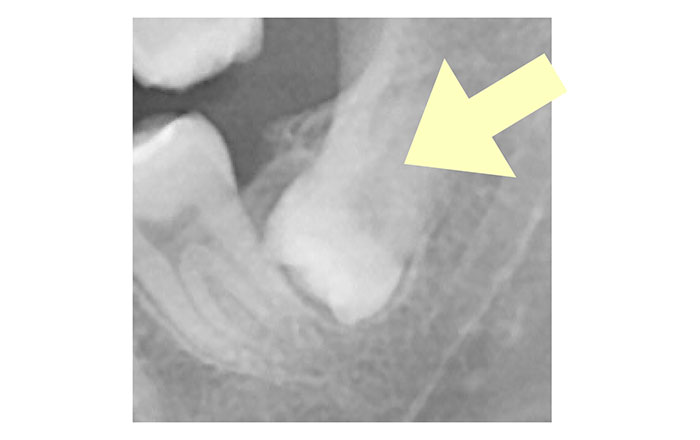

3.歯ぐきに埋まっている親知らず

歯ぐきに埋まって生えている、上下の親知らずの抜歯の場合です。

難易度は普通〜難しいです。

時間は30分〜90分ほどで、保険適用内だと治療費は4,000〜5,000円ほど、自由診療だと治療費は22,000円(税込)です。

親知らずを抜く時に気をつけなければいけない顎の神経を三叉神経と言い、特に下顎神経と言われるものが関わっています。

抜歯する時に神経を傷付けてはいけないので、神経との近さをレントゲンで調べますが、親知らずと神経との距離の近さにより、診査診断も異なります。